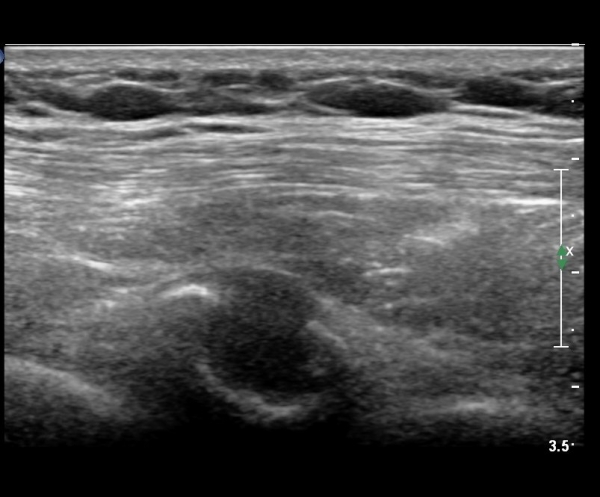

on moving of prove a little, there is bony protrusion(osteoblastic lesion) and hypoechoic(osteolytic)  lesion(image 2, 3, 4).

in transverse scan, visualization of osteoblastic mass with central osteolytic lesion(image 5, 6).

If there is no trauma history  or visualization of callus so ealry , doctor consider the possibility of tumors of rib.

As like this case, visualization of osteoblastic lesion and osteolytic lesion in simultaneously  suggests a malignant mass.